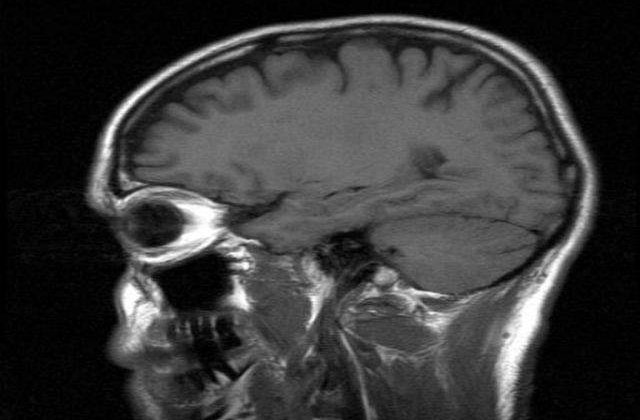

Echipa de cercetatori de la Medical Research Council a efectuat studiul folosind imagistica prin rezonanta magnetica asupra a 484 de voluntari sanatosi, cu varsta cuprinsa intre 8 si 85 de ani. Savantii au vrut sa vada cum se modifica creierul, in mod natural, pe masura ce oamenii inainteaza in varsta.

Datele obtinute au aratat existenta unui model comun: partile creierului care se dezvolta ultimele sunt primele care arata semne de degradare cauzata de imbatranire, scrie MEDIAFAX.

Aceste regiuni cerebrale - o retea de neuroni sau materie cenusie - lucreaza cu informatii foarte importante, "prioritare", furnizate de diferitele simturi ale organismului, cum sunt vazul si auzul.

Cercetatorii au analizat datele obtinute de la pacienti bolnavi de Alzheimer si altii bolnavi de schizofrenie si au descoperit ca in ambele cazuri sunt afectate aceleasi regiuni din creier.